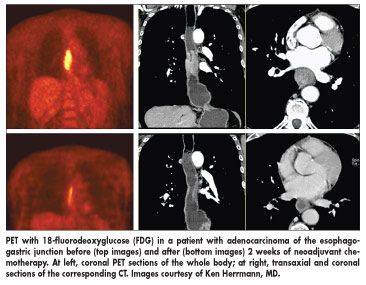

The study, part of the MUNICON trial, was designed to determine whether PET could discern between those patients who would benefit from neoadjuvant chemotherapy and those who would not respond and therefore lose valuable time and suffer side effects with no corresponding benefit. Researchers used 18-fluorodeoxyglucose (FDG) with PET to make their decisions.

Patients with a greater than 35% decrease of tumor standardized uptake value (SUV) after 2 weeks of neoadjuvant platin/5-fluorouracil-based chemotherapy, compared with baseline, were defined as metabolic responders. They continued on chemotherapy for 12 weeks before surgery.

Patients with less than a 35% SUV decrease were classified as metabolic nonresponders. Chemotherapy was stopped after the initial 2 weeks for nonresponders, and they proceeded to immediate surgery. Follow-up CT scans and endoscopy were performed every 3 months in the first year and every 6 months thereafter.